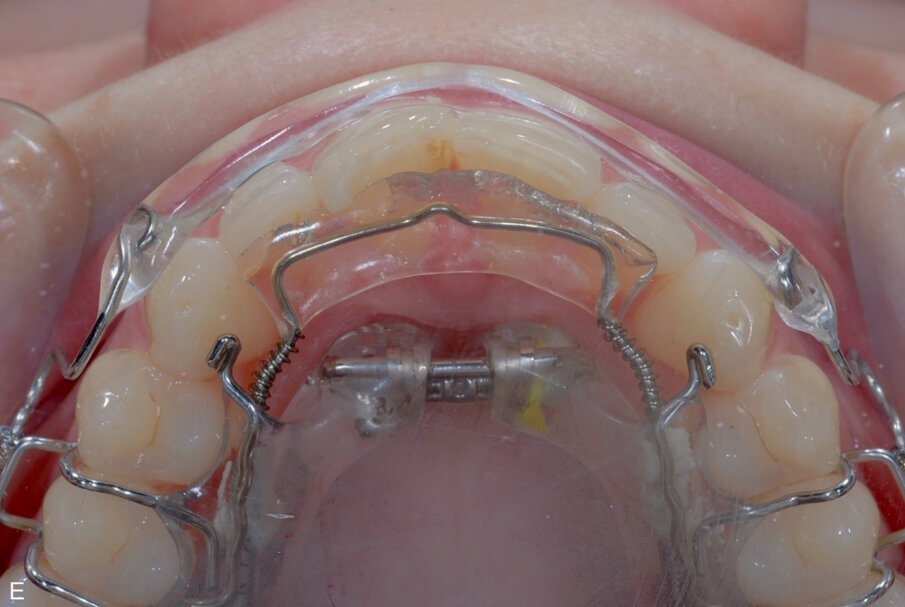

Fig. 9: ClearSmile Inman Aligner fitted

At the initial appointment, palatal anchors were placed, with interproximal reduction (IPR) and predictive proximal reduction (PPR) carried out using the guide issued from the laboratory. The patient was instructed on how to turn the expander. Aligner in situ. At the initial appointment, palatal anchors were placed, with interproximal reduction (IPR) and predictive proximal reduction (PPR) carried out using the guide issued from the laboratory. The patient was instructed on how to turn the expander. Aligner in situ. |

• Remove anchor from UR1 to drive out UL1 before starting the rotation of UR1.

• Wait for the front teeth to unwind, focusing on the expansion.

• Don't turn the expander too quickly as it will induce unwanted tooth movement.